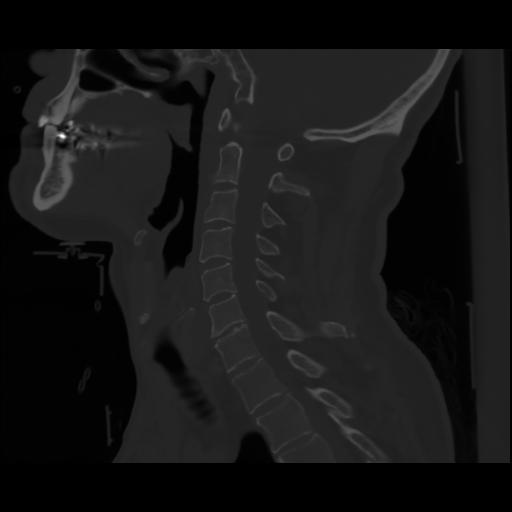

14 P.BLANDAS,,Sagittal,2.000,P.BLANDAS,Sagittal,